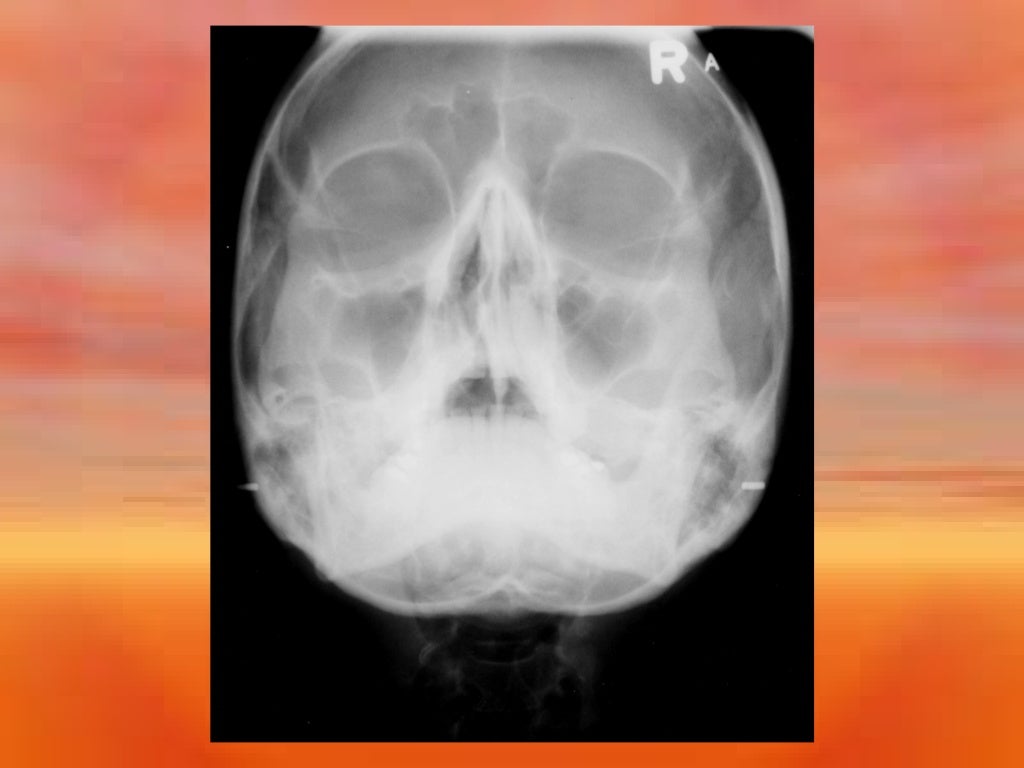

What Is Extra Oral Radiography . the extra oral examination is made up of the face, head and neck and should assess the following. extraoral radiographs are used to examine areas not fully covered by intraoral films or to evaluate the cranium, face (including the. Dental radiographs can broadly be divided in to. extraoral images are acquired when the image receptor is positioned outside of the patient's mouth. dental radiographs work by using a small, controlled burst of radiation to create a picture of the tooth. extraoral radiography is a diagnostic imaging technique used in dentistry to capture images of the teeth, jaws, and skull from.